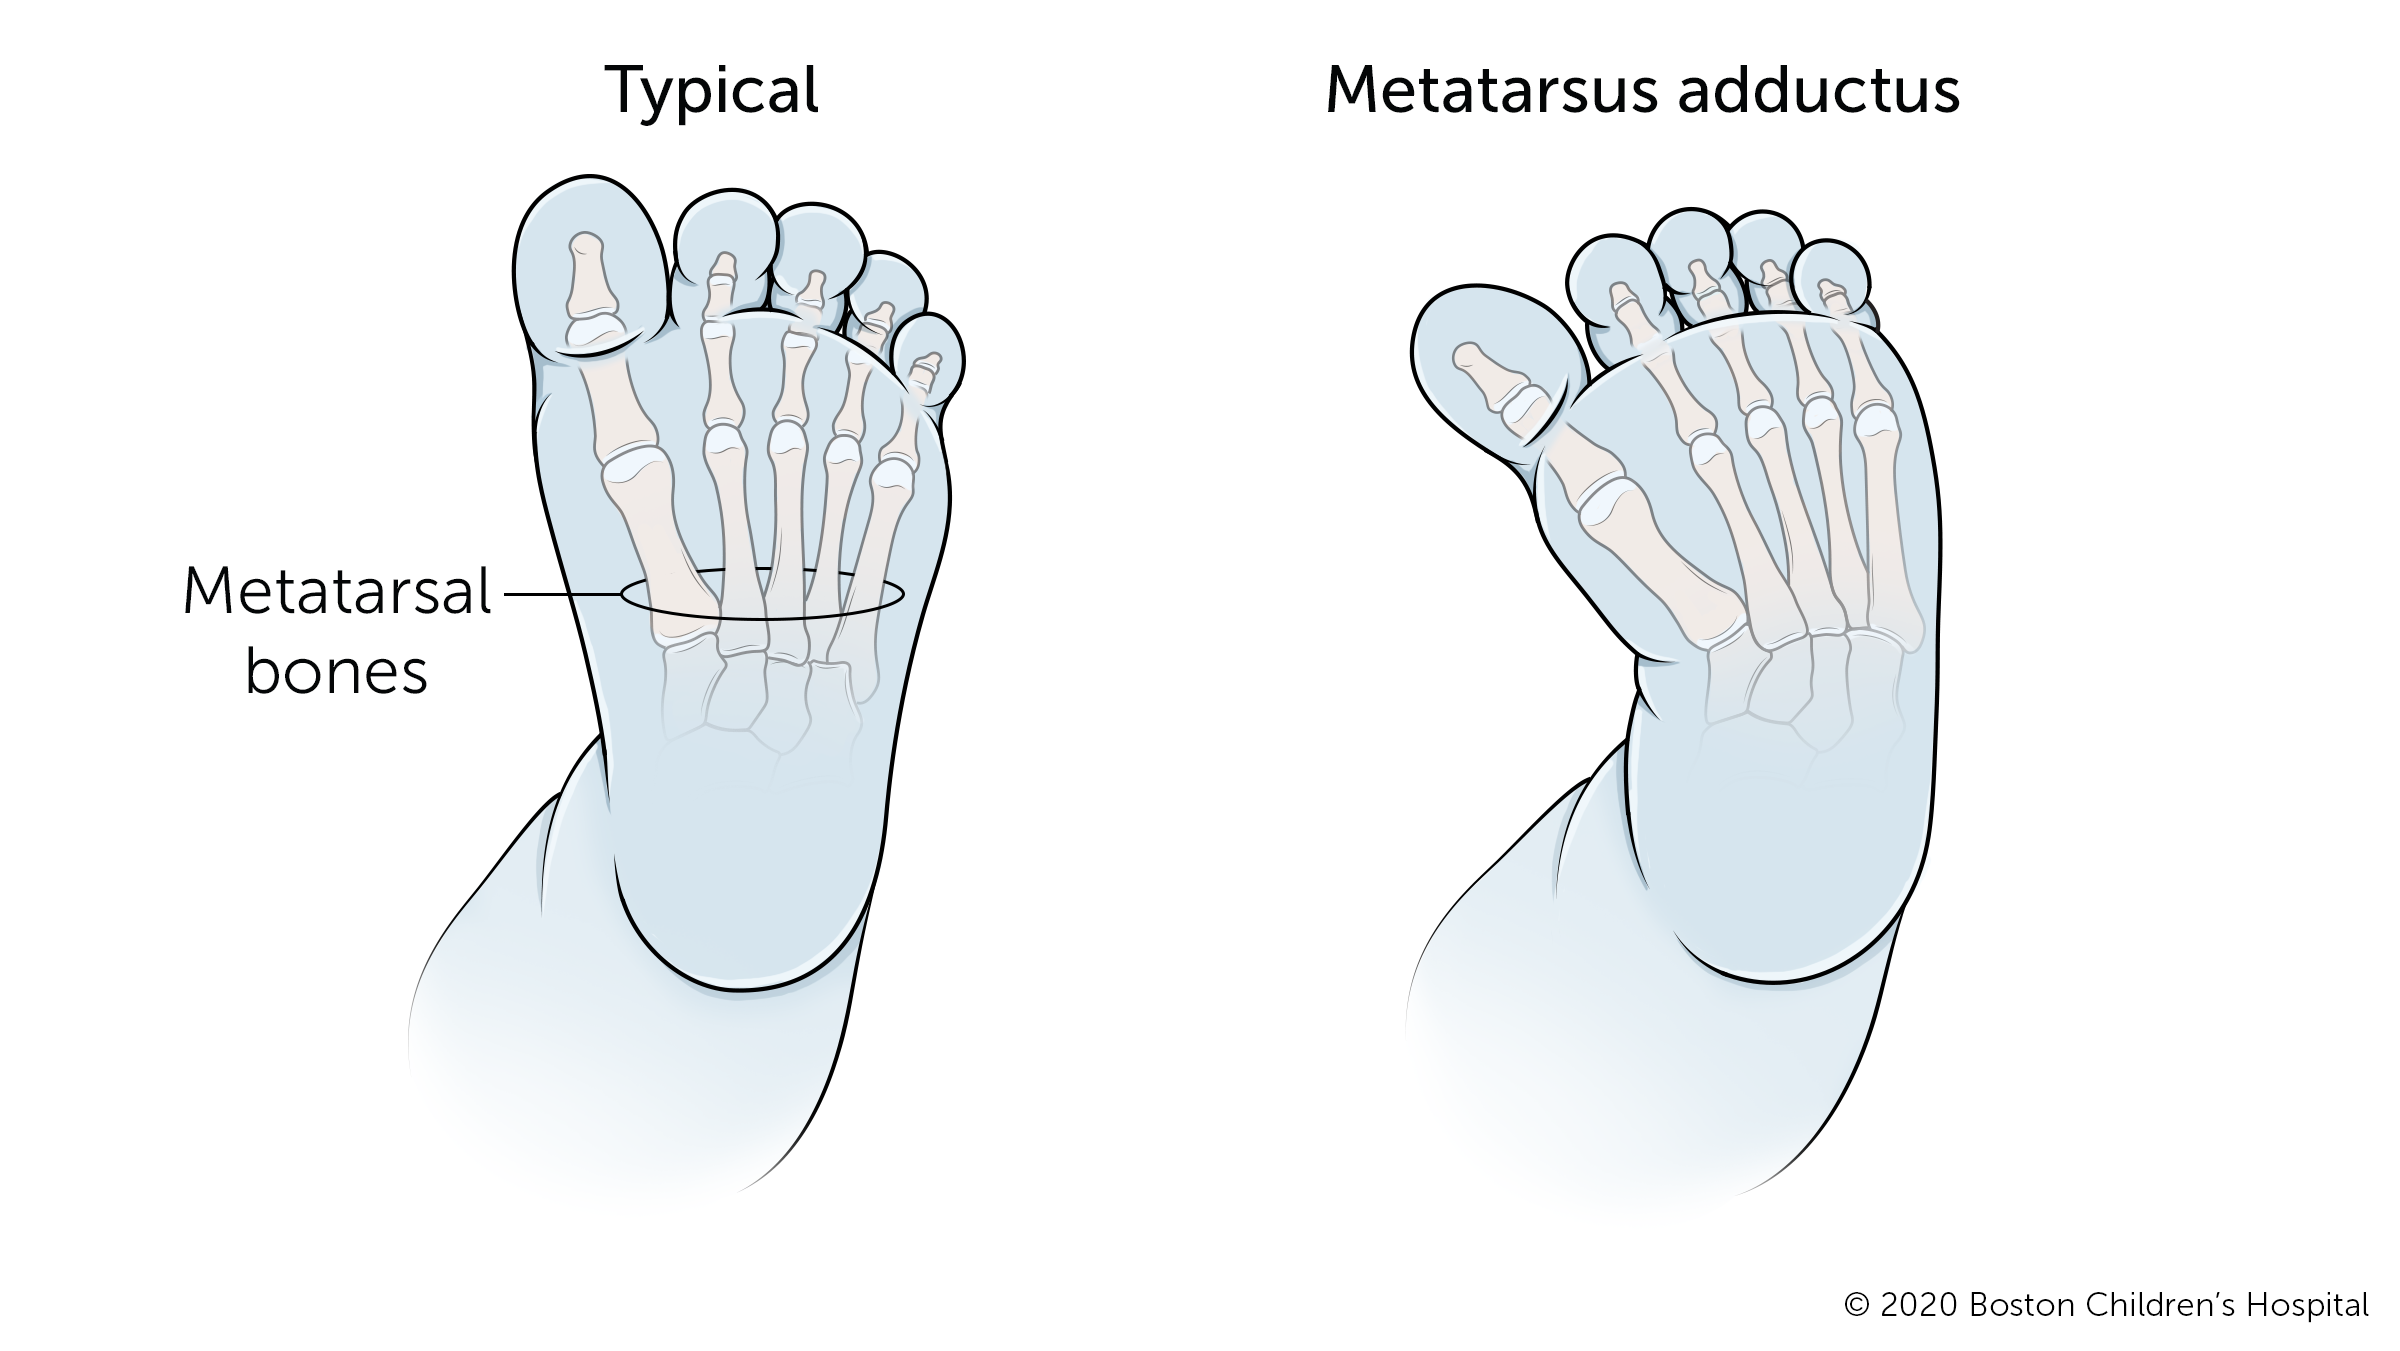

Metatarsus adductus

Metatarsus adductus is a common positional deformity that causes a child's feet to bend inward from the middle of the foot to the toes. In severe cases, it may resemble clubfoot. The condition improves on its own most of the time.

Babies with severe metatarsus adductus may need treatment, which usually involves special exercises, casts, or special corrective shoes. These treatments have a high rate of success in babies from 6 to 9 months old.